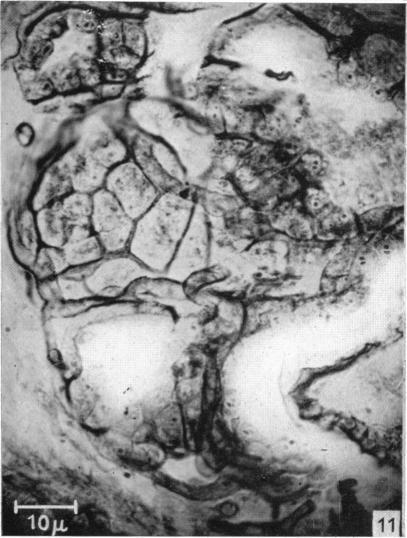

The silver staining of myoepithelial cells, particularly in the mammary gland, and their relation to the ejection of milk.

J Anat. 1952 Jan;86(1):49-57.